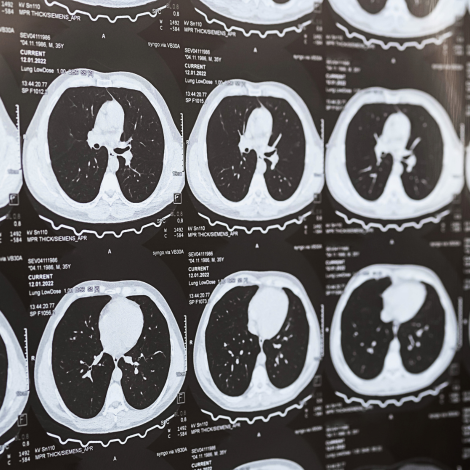

Chest CT

Doctors use chest CT to: examine abnormalities found on chest X-rays; help diagnose the causes of signs or symptoms of chest disease, such as cough, shortness of breath, chest pain, or fever; detect and evaluate the extent of tumors that arise in the chest, or tumors that have spread there from other parts of the body; assess whether tumors are responding to treatment; help plan radiation therapy; evaluate injury to the chest, including the heart, blood vessels, lungs, ribs and spine.